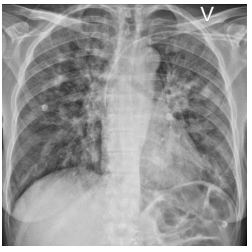

A 47-year-old female with IgA nephropathy developed a severe respiratory failure six weeks after kidney transplant. The patient had high levels of human leukocyte antigen antibodies, and according to the Norwegian transplantation program, a high-risk immunosuppression regimen was required. This includes tacrolimus, mycophenolate mofetil (MMF), basiliximab, rituximab, intravenous immunoglobulins (IVIG), and high-dose methylprednisolone (500mg) [8, 9]. Additionally, the patient received prophylactic P. jirovecii treatment with trimethoprim sulfamethoxazole [10]. Postoperatively, the kidney transplantation was considered successful with a well-functioning graft. Four weeks after the transplantation, she was re-scheduled for surgical fenestration of a kidney-close lymphocele (defined as Day 0). During anaesthetic induction, intubation was disrupted due to aspiration. During the following week the patient became increasingly dyspnoeic with stridor and was transferred to the ICU for closer surveillance and non-invasive ventilation support. Her chest x-ray on Day 13 showed bilateral patchy infiltrates as in bronchopneumonia (Figure 1).

Figure 1: Chest X-ray taken on Day 13 showing bilateral patchy infiltrates. (V = left).